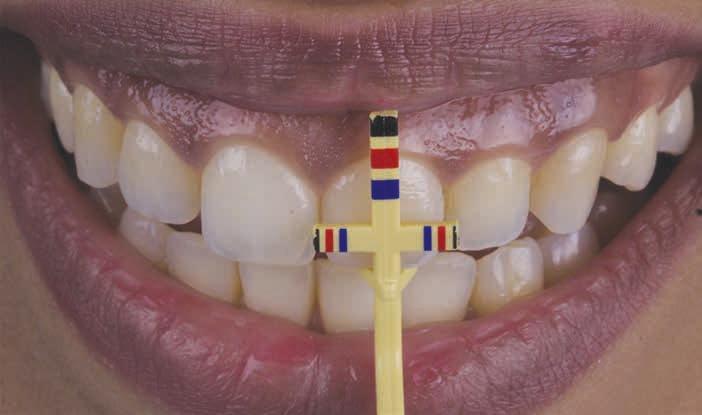

Chu Proportion Gauges

Chu proportion gauges were introduced by Stephen Chu in 2007.30 He proposed the use of 2 different proportion gauge tipsdthe T-bar (Figure 3) and in-line gauges. They determine the ideal clinical crown length to width ratio following a predetermined proportion of 78%, for which the appropriate gingival margin

position and tooth dimension could be anticipated without a subjective estimation.30 This technique relies on the following clinical parameters: gingival width, gingival margin position relative to the CEJ, crown width, clinical crown length, anatomic crown length, and distance between the CEJ and alveolar crest.30,31

The osseous level is assessed before flap elevation on the basis of the measurements obtained by means of bone sounding technique or gauge.28,32,33 After the flap is elevated, the appropriate proportion of supracrestal attached tissue and amount of osseous resection can be planned and carried out using a periogauge or crown lengthening gauge.29,32 Such gauges estimate the desired crown length and enable the clinician to determine the future location of the alveolar crest to be 3 mm away from the CEJ facially, tapering toward the interdental area.29,32

The esthetic crown lengthening procedure guided by Chu proportion gauge has been found to achieve predictable and stable postsurgical outcomes related to supracrestal attached tissue and gingival margin position.33 In addition, it overcomes the disadvantages of additional cost and dental visits required to fabricate a surgical stent. However, the practical use of proportion gauges cannot be applied to worn or modified dentition, as the presence of intact incisal edges is crucial for successful outcomes.34

Figure 3. Chu proportion gauge (T-bar).